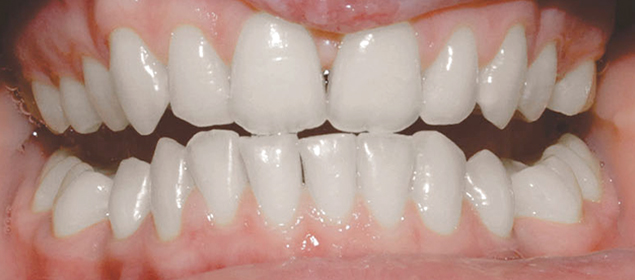

>   Stripping zębów siecznych górnych (wachlarzowaty kształt).

•  Aby poprawić kształt zębów przednich – w przypadku zębów trójkątnych, beczułkowatych czy wachlarzowatych. Dzięki strippingowi można uniknąć powstawania ciemnych przestrzeni między zębami, co poprawia estetykę uśmiechu.